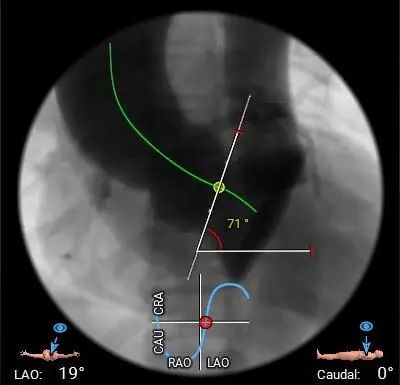

主动脉瓣环水平夹角71度,严重横位心,主动脉弓宽度、角度尚可,弓部存在散在钙化

虚拟瓣环与水平夹角